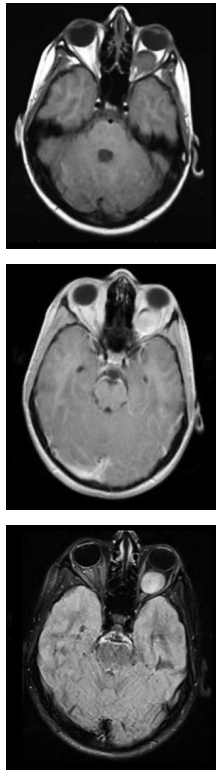

Adolescente, 14 anos, com queixa de perda progressiva da acuidade visual à esquerda.

Após a realização do exame de imagem, pode-se afirmar que: